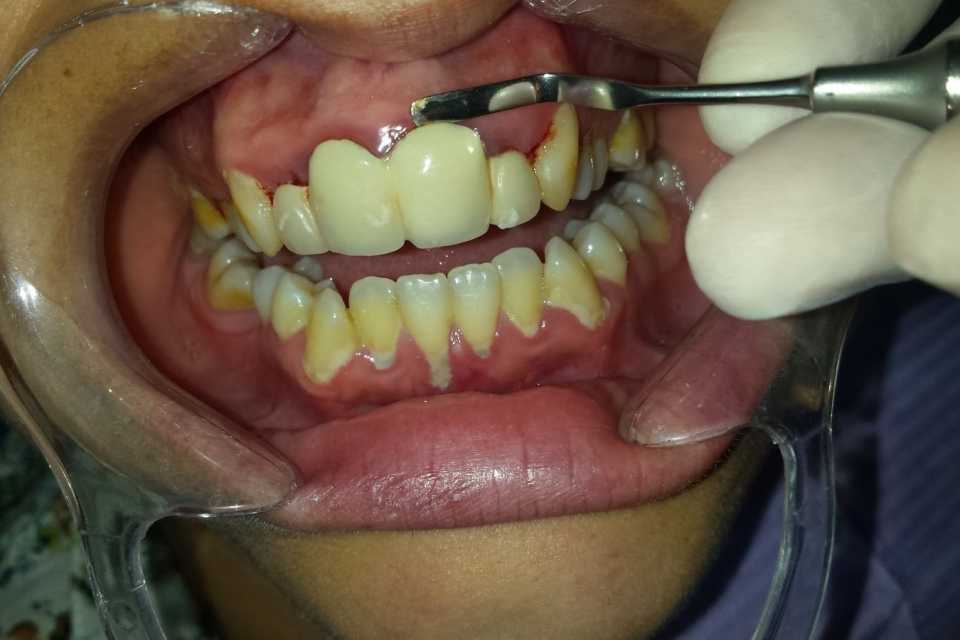

Pacienta, în vârstă de 28 de ani, s-a prezentat din motive estetice, acuzand un miros neplăcut și sângerarea gingiilor. Am recurs la îndepărtarea vechii lucrări, refacerea tratamentelor de canal precum și a bonturilor protetice. Gingia prezenta o iritație cronică, dar prin adaptarea corectă a noii lucrări ceramice, aceasta și-a recăpătat aspectul natural. Fiind o zonă estetică importantă am apelat la o lucrare metalo-ceramica (Ivoclar D'sign).

Coroanele dentare au scopul de a readuce la forma naturală și la starea de normală funcționare, un dinte deteriorat.